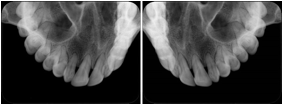

Intra-oral radiography typically involves acquisition of multiple images of various parts of the dentition. Many digital radiographic systems offer customized templates that are used for displaying the images in a study on the screen. These templates may also be referred to as mounts or view sets. The Structured Display Object represents a standard method of encoding and exchanging the layout and intended display of Structured Displays. A structured display object created in this manner could be stored with a study and exchanged with images to allow for complete reproduction of the original exam.

1. A patient visits a General Dentist where a Full Mouth Series Exam with 18 images is acquired. The dentist observes severe bone loss and refers the patient to a Periodontist. The 18 images from the Full Mouth Series along with a Structured Display are copied to a DICOM Interchange CD and sent with the patient to see the specialist. The Periodontist uses the CD to open the exam in his Dental Radiographic Software and consults via phone with the General Dentist. Both are able to observe the same exam showing the images on each user's display using the exact same layout.

Intra-oral Full Mouth Series Structured Display

Figure OO-1. Intra-oral Full Mouth Series Structured Display